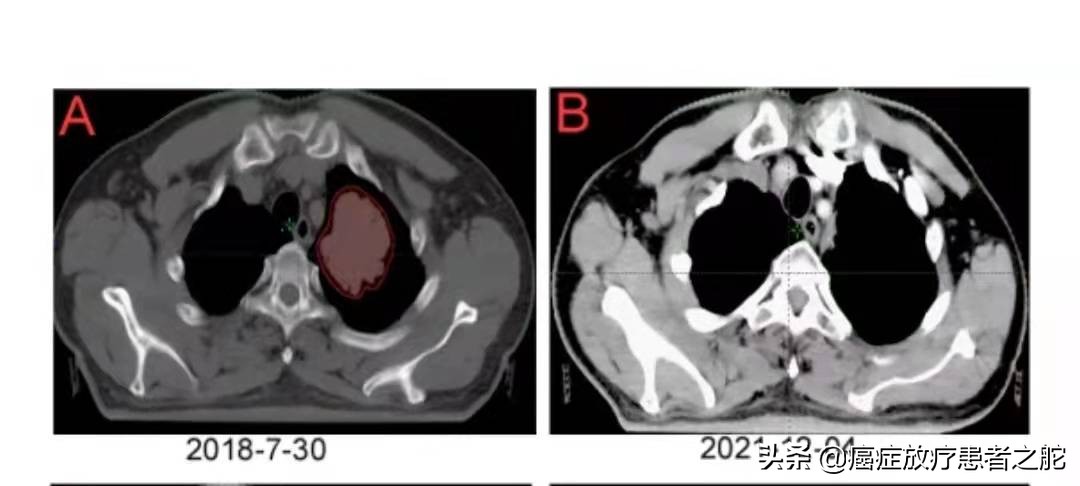

2018年,眼看着肺内转移灶,越来越大,遂对患者左肺转移灶进行了精确放疗。具体如下:

近期患者到医院复查,肺内转移病灶,放疗后彻底消失。而且,去年上半年,肝脏复发区域,也进行了放疗干预,这次复查,提示效果也很不错。具体如下图所示: